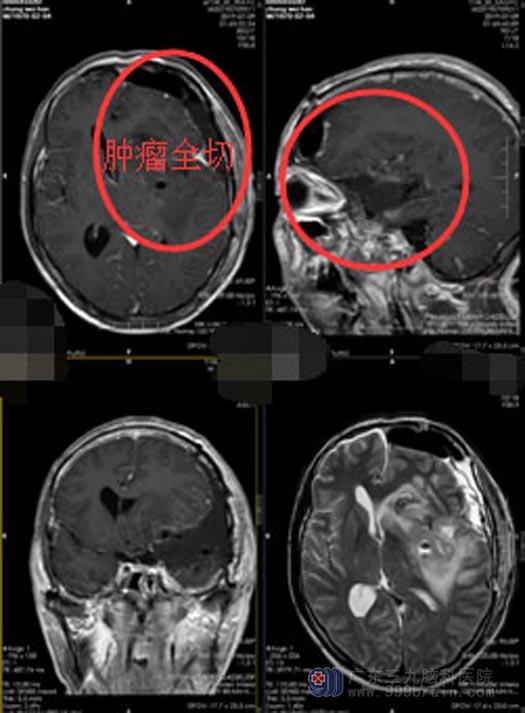

老张和家属对手术医生的充分信任,使得医生也有了更大的信心。老张入院的第三天就实施了手术治疗,手术非常成功,颅内血管、语言区保护完整,肿瘤全切。术后病理结果显示:淋巴细胞浆细胞型脑膜瘤,良性肿瘤。